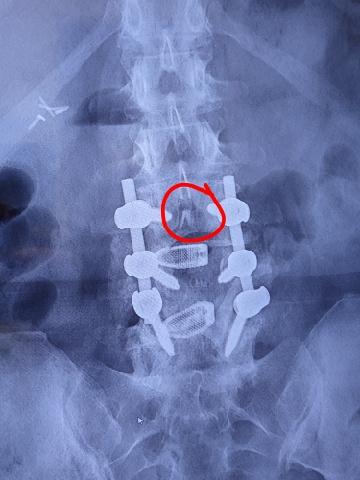

I had back surgery on April 24, 2024 for spinal stenosis and degenerative disc disease. My doctor placed two rods and six pins in my back. A year later, he recommended another surgery to extend the hardware from L3 to the pelvic bone—longer rods and four more pins. After I explained everything to my friend Kevin, he encouraged me to start taking BoneX. Six months later, my follow-up showed new bone growth, and I no longer needed the extension surgery. Instead, my doctor removed the rods and pins that were there—and even let me keep them to show my family and friends!